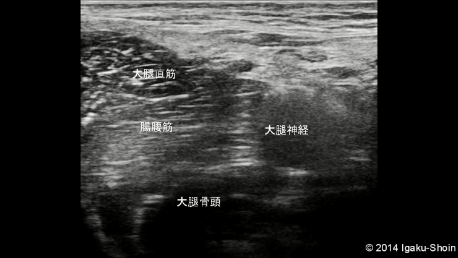

本書は症例形式で、疾患にかかわる筋の超音波解剖を通して、運動療法の「なぜ?」を解説。超音波解剖(エコー)では、触診ではわからない深部の筋の動きを見ることができる。この症状にはなぜこの運動療法が効果的なのか? 運動療法で筋の動きはどう変わるのか? その実際を超音波画像(動画)で確認しながら、運動療法のコツを理解できる1冊。